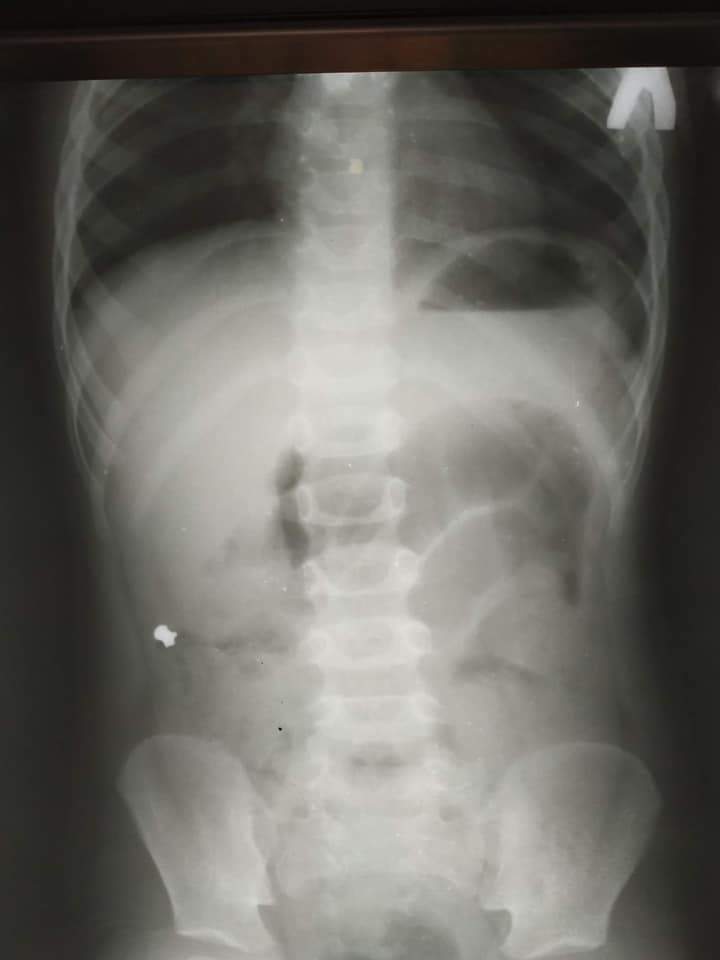

Хлопчик потрапив до лікарні з болями у животі. На рентген-знімку животика дитини лікар побачив нетипову знахідку – кулю від гвинтівки.

- Лікар побачив, що у дитини справа в животі розміщена куля від пневматичної гвинтівки.

Хлопчик проковтнув кулю від пневматичної гвинтівки / Фото ОХМАТДИТу

Якби куля потрапила зі шлунка в кишківник, то вона б просто вийшла через пряму кишку й не спричинила б запалення апендиксу. Проте куля, яка потрапила до животика хлопчика, подолала незвичний шлях – замість потрапити у пряму кишку, куля-мандрівниця опинилася в апендиксі, тому й стала причиною запального процесу у ньому.

Куля стала причиною запалення апендиксу / Фото ОХМАТДИТу